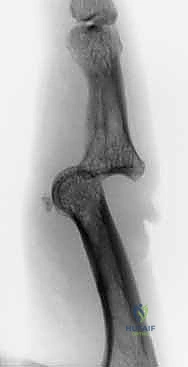

- Identify Distal Wire Level: Under image intensifier guidance, identify an appropriate level in the distal half to two-thirds of the middle phalanx. This placement must be distal to any fracture extension in the shaft of the middle phalanx to ensure adequate purchase in healthy bone. Mark this level on the skin.

> PEARL: For pilon fractures with significant distal extension, the distal wire can be placed as far distally as the head of the middle phalanx, or even near the center of rotation of the distal interphalangeal (DIP) joint. The middle phalanx is often narrowest proximally, so a more distal placement often provides a wider bone segment for easier and more secure wire placement. I have never encountered a fracture so distal that adequate fixation could not be achieved.

Figures 1D and 1E (TECH FIG 1D,E) illustrate finding and marking the position of the distal wire. Note how this placement is more distal than average, towards the head of the middle phalanx, due to an associated DIP joint injury, providing ample bone for fixation.

-

Initial Distal Wire Insertion: Similar to the proximal wire, insert the 1.1-mm K-wire percutaneously, aiming for the center of the middle phalanx. This wire must be perpendicular to the long axis of the finger and, crucially, parallel to both the plane of rotation of the PIP joint and the previously inserted proximal wire. This parallelism is essential for creating a functional dynamic construct.

Fluoroscopic Confirmation (Partial Insertion): Insert the wire partially through the middle phalanx and check its position carefully with both PA and lateral views on the image intensifier.

*Figures 1F and 1G (TECH FIG 1F,G) confirm the insertion and position of the distal wire on the image intens